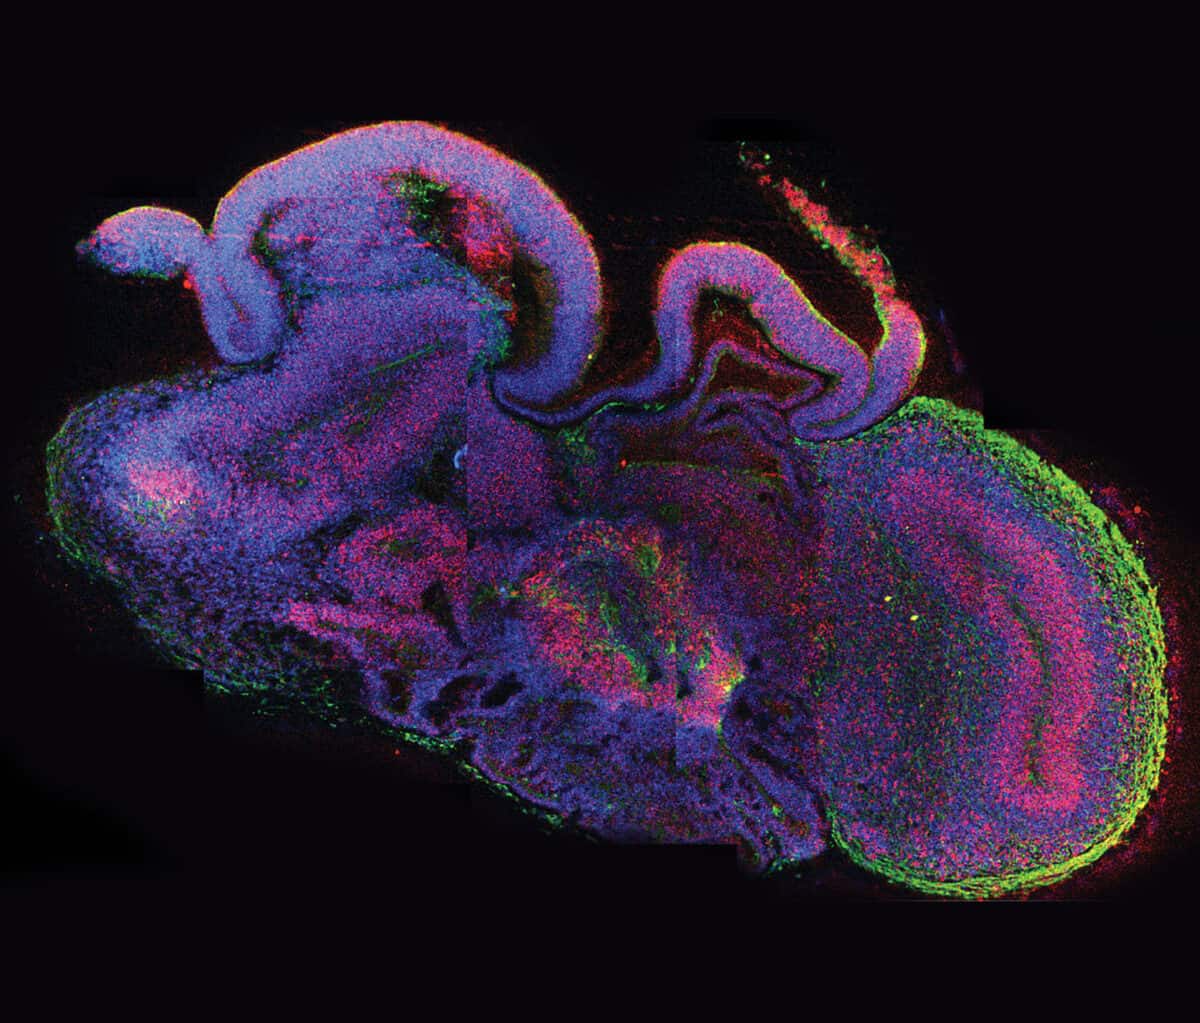

An organoid is a simplified version of an organ grown from a single human cell. Organoids are small, typically about the size of the head of a pin, though some may grow slightly larger. For her brain organoids, Lancaster started with skin cells from a patient with microcephaly, which carried the gene known to cause the condition, and also from a healthy control. She “reprogrammed” these mature skin cells to become induced pluripotent stem cells (iPS), which can become any type of cell in the body. Then she coaxed these iPS cells to develop into tiny versions of her subjects’ brains.

During the next two to three months, the cells began to organize themselves into layers and clusters of different cell types, paralleling what happens during the first eight to 10 weeks of human fetal brain development. Some cells differentiated themselves into various types of the nerve cells (neurons) found in several brain regions, while others remained “neural progenitors,” creating a reservoir of potential neurons to be used later. Producing such self-assembling organoids “doesn’t require any super-sophisticated bioengineering,” Knoblich told Nature in 2015. “We just let the cells do what they want to do, and they make a brain.”

In the organoids that Lancaster had derived from a healthy person, the growth of the hindbrain slowed as the forebrain grew—reflecting what happens as a normal human fetal brain develops. Organoids grown from the cells of a patient carrying the gene for severe microcephaly, however, didn’t grow as large because those brain regions didn’t develop properly. Further research showed that too many neural progenitors in these organoids had become neurons early on, leaving the developing brain without the resources it would have used to enlarge the forebrain.

Lancaster and Knoblich published their work in Nature in 2013, at a time when microcephaly was still rare. But two years later the Zika virus outbreak hit, and physicians noticed that many women bitten and infected by virus-carrying mosquitoes gave birth to babies with microcephaly. To determine whether the Zika virus caused this, a number of independent teams of researchers—including two in Brazil and one at the University of California, San Diego—created brain organoids from healthy human cells and infected some of them with the Zika virus.

Most of the Zika-infected organoids grew to barely half the size of their uninfected counterparts. The Zika virus also replicated the genetic defect in another way, depleting the progenitor cells and causing similar development problems to the ones that Lancaster had observed in Vienna. This experimental proof that the Zika virus caused microcephaly came quite rapidly, and other teams working with Zika have continued to use organoids to test therapeutic interventions and to probe why only some strains of the virus appear to result in the condition.

Not only can organoids potentially offer a better model for human disease, they can also be surprisingly easy to coax into being. Given the correct chemical prompts, cells follow their internal instructions and spontaneously organize themselves. “We kept them healthy, and without giving them many instructions on what kind of cells they should become they produced many of the cells present in the human brain and achieved the formation of complex tissue,” says Arlotta, describing the brain organoids she used in research published in Nature in May 2017.

For that study, Arlotta was looking at a stage of brain development later than the one studied in the microcephaly and Zika experiments, which modeled only what happens early on during pregnancy. So she modified the Lancaster system to allow her organoids to survive and develop in culture for longer than anyone else—more than nine months.